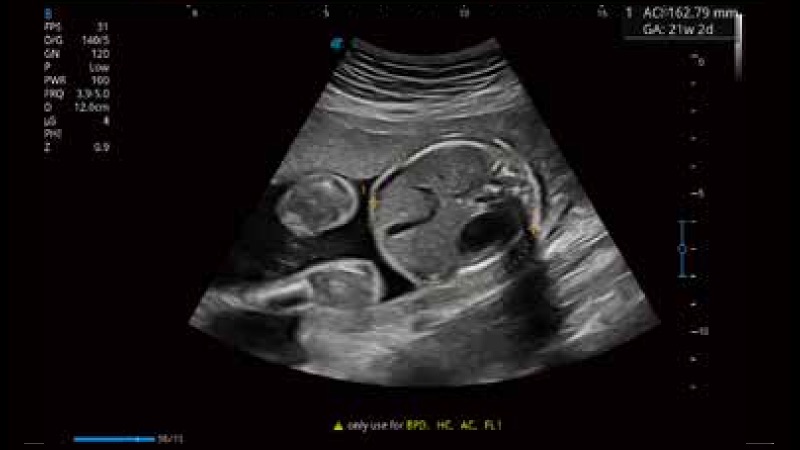

開(kāi)立醫(yī)療通過(guò)不斷的技術(shù)創(chuàng)新,為大眾的生命健康提供持續(xù)關(guān)愛(ài)。P12 Plus采用全新一代超聲成像平臺(tái),新平臺(tái)旨在將真實(shí)還原組織解剖結(jié)構(gòu)作為首要目標(biāo)。平臺(tái)采用全新集成化硬件模塊,搭載新一代芯片,系統(tǒng)性能得到大幅提升,為您的診斷提供了豐富的臨床信息。優(yōu)異的圖像表現(xiàn),豐富的探頭配置,全面的應(yīng)用功能,為您日常診斷提供了可靠的助手。

彩色多普勒超聲診斷系統(tǒng)